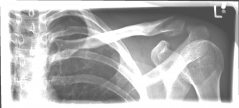

Acromioclavicular (lateral clavicular fracture), should be treated surgically, as a conservative therapy often leads to the formation of a so-called pseudarthrosis. Various implants are available, such as the hook plate and an anatomically preformed angular stable lateral clavicle plate.

Schlüsselbein 2                  Schlüsselbein 3

Images: A lateral clavicle fracture was treated with a hook plate. The hook is fixed under the acromioclavicular, while screws anchor the plate in the collarbone.